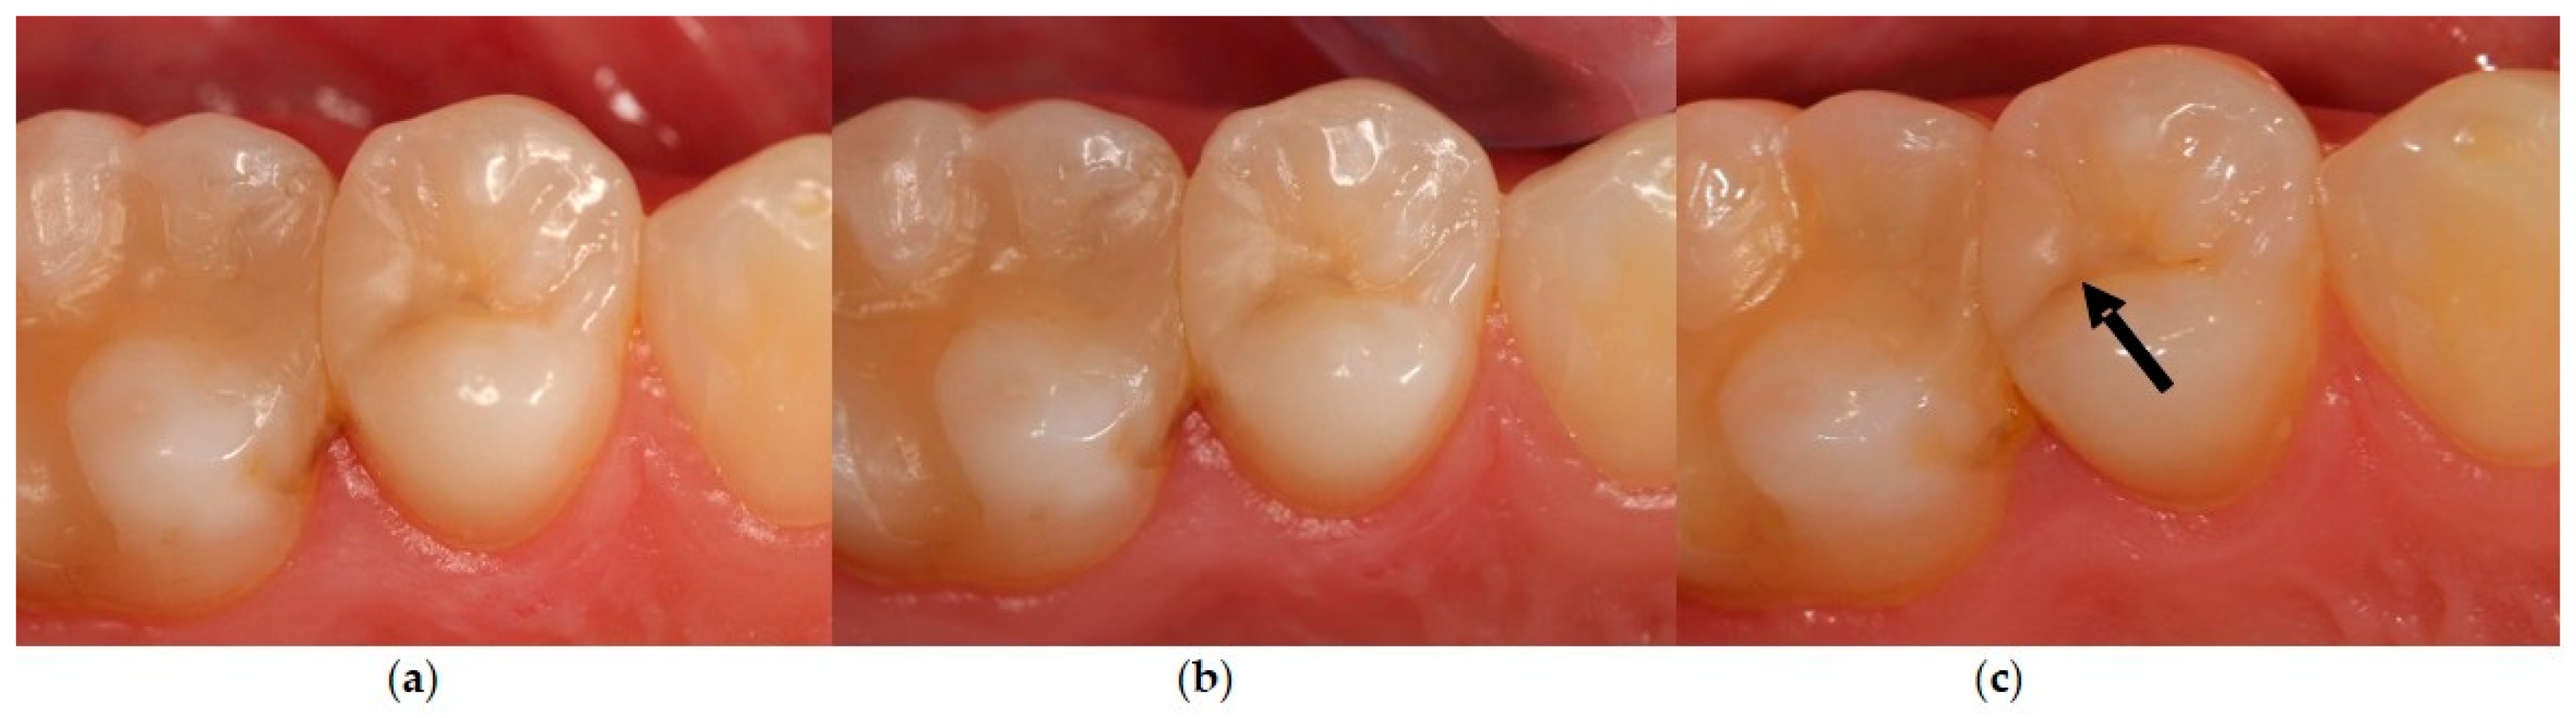

3.4.6. Marginal Discoloration